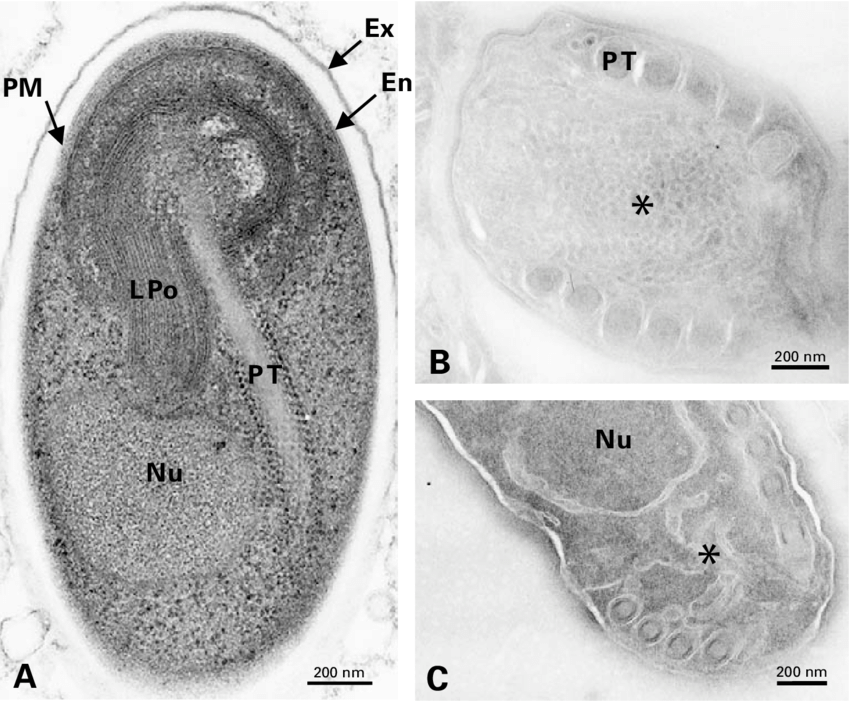

Electron microscopic image of E. cuniculi spores.

Vanessa Taupin. La diff´erenciation sporale chez les microsporidies : imagerie 3D et isolement des stades de d´eveloppement, analyse de l’expression diff´erentielle de prot´eines structurales et premi`ere identification des glycanes. Genetics. Universit´e Blaise Pascal - Clermont-Ferrand II, 2006. French